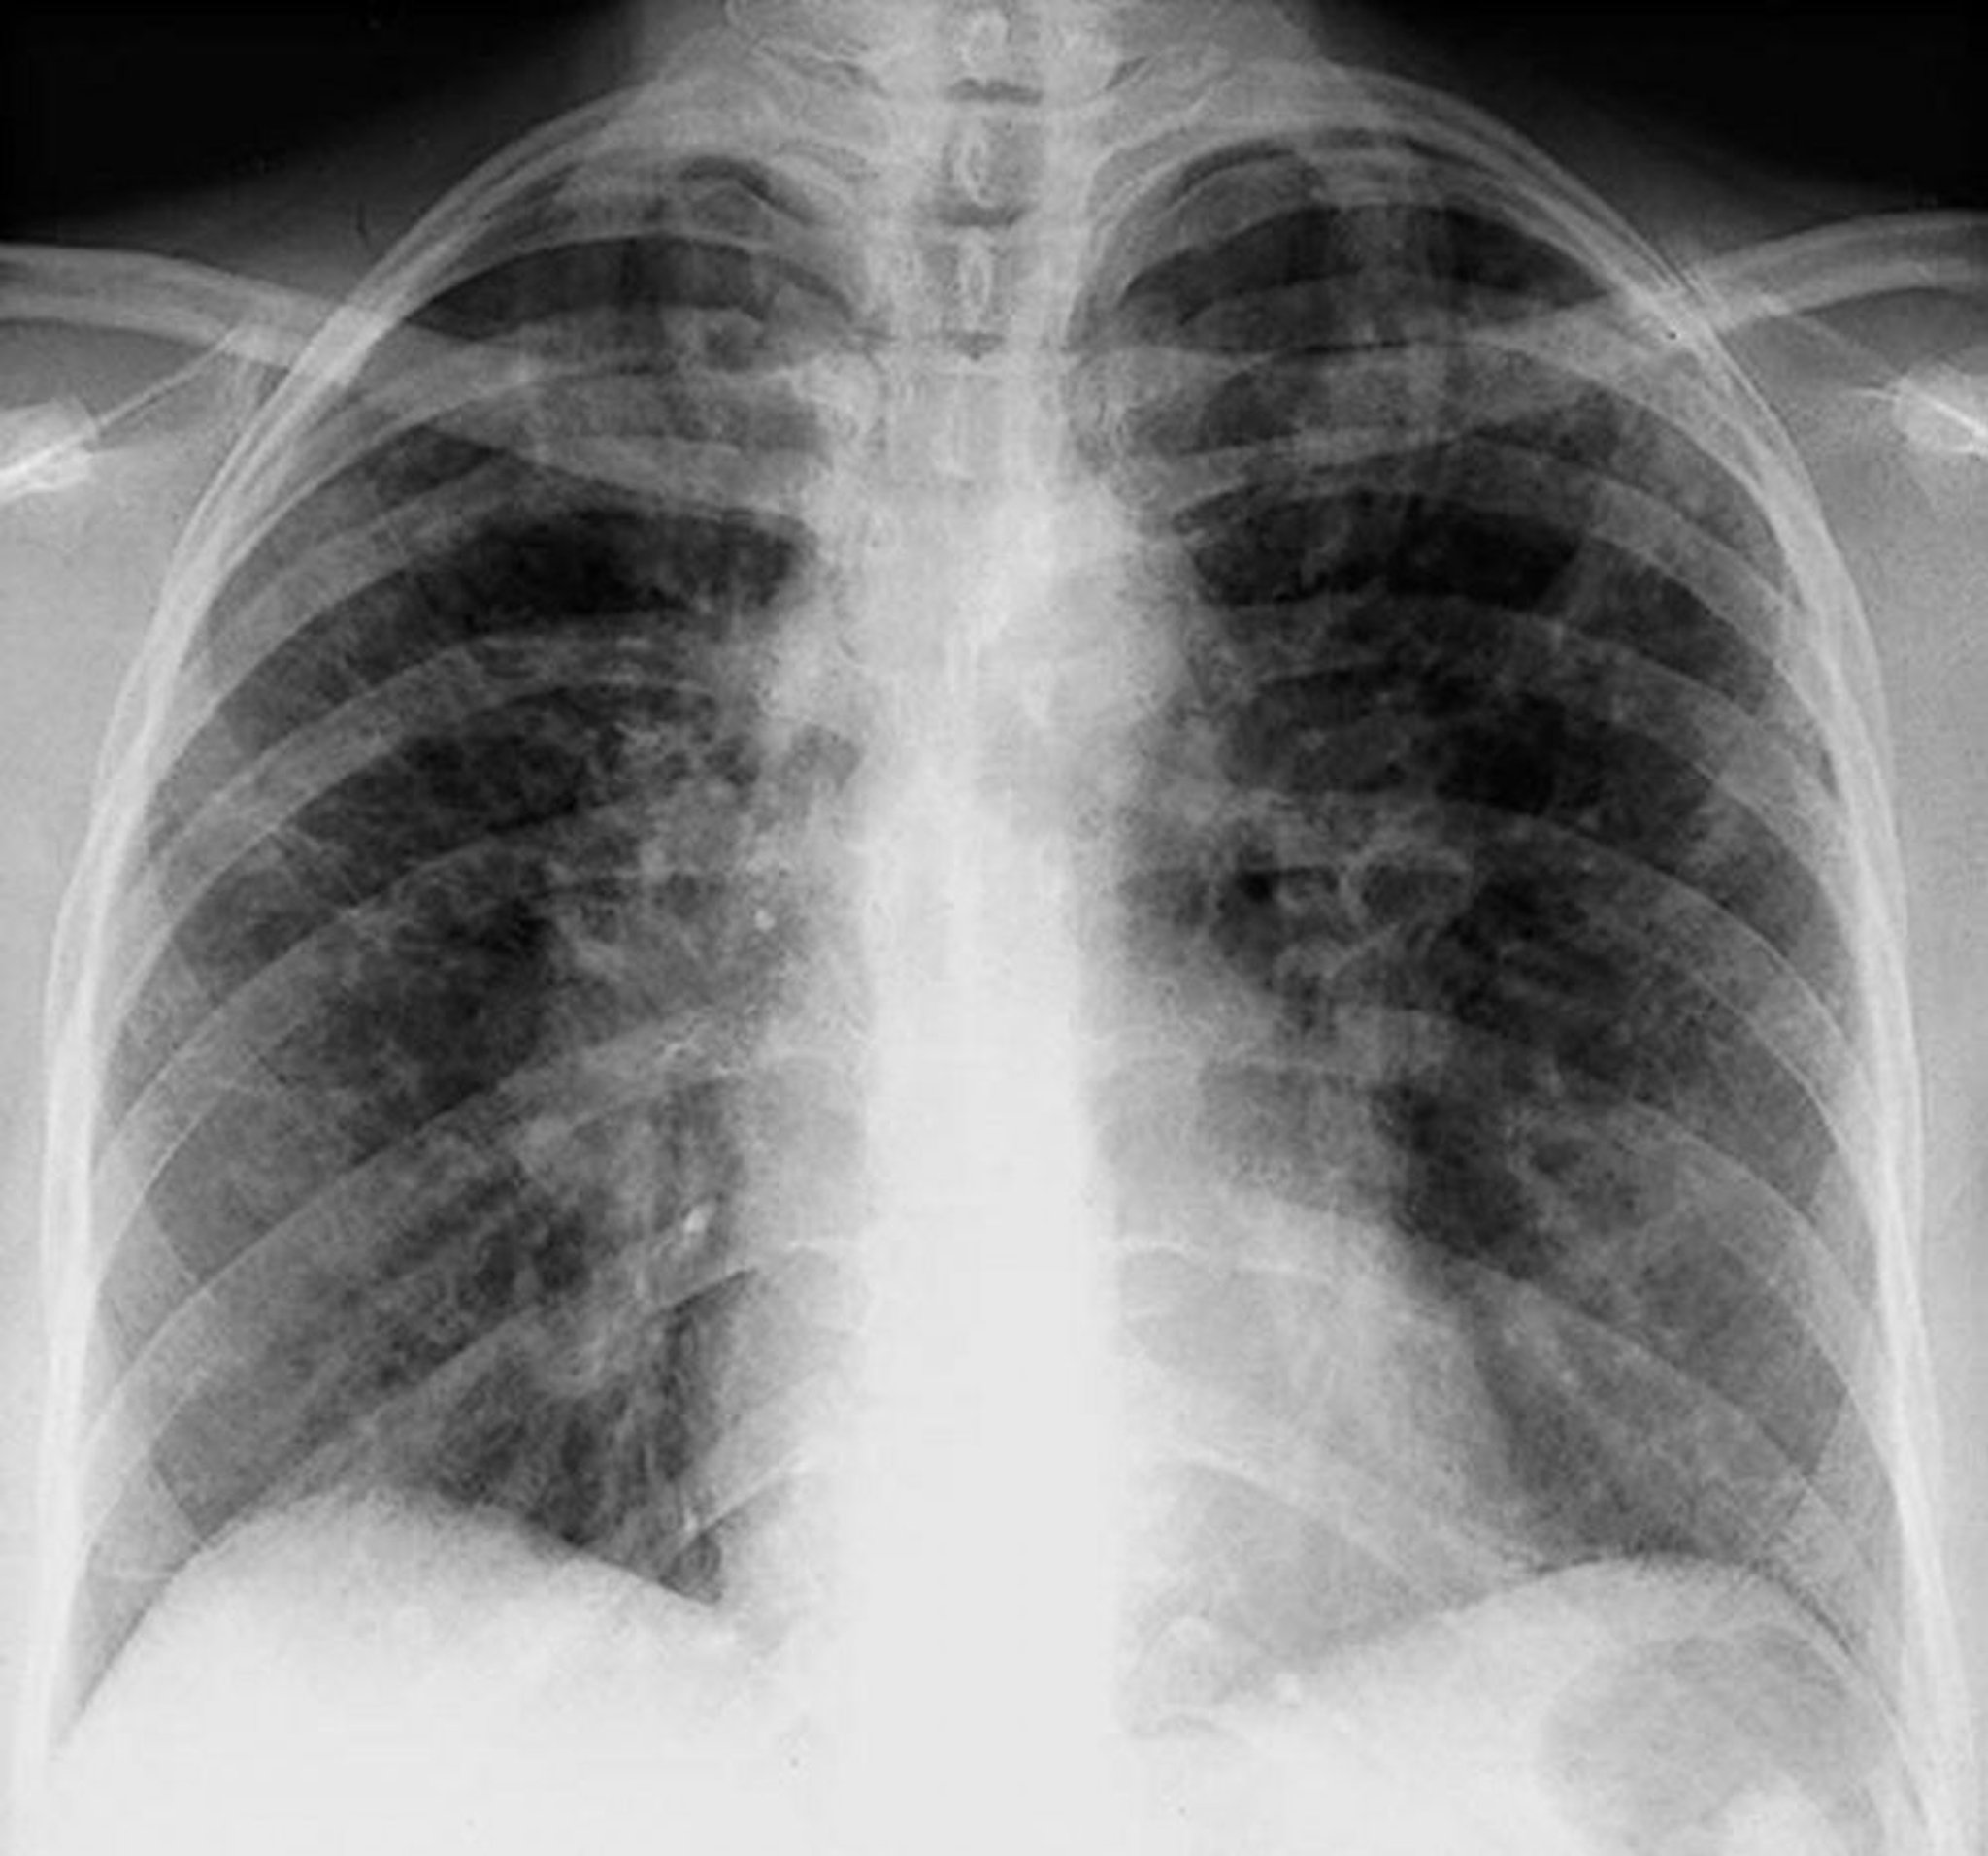

Sarcoidose (estágio II)

Adenopatia hilar bilateral com opacidades intersticiais na sarcoidose em estágio II.

By permission of the publisher. De Tanoue L, Elias J. In Bone's Atlas of Pulmonary and Critical Care Medicine. Edited by J Crapo. Philadelphia, Current Medicine, 2005.